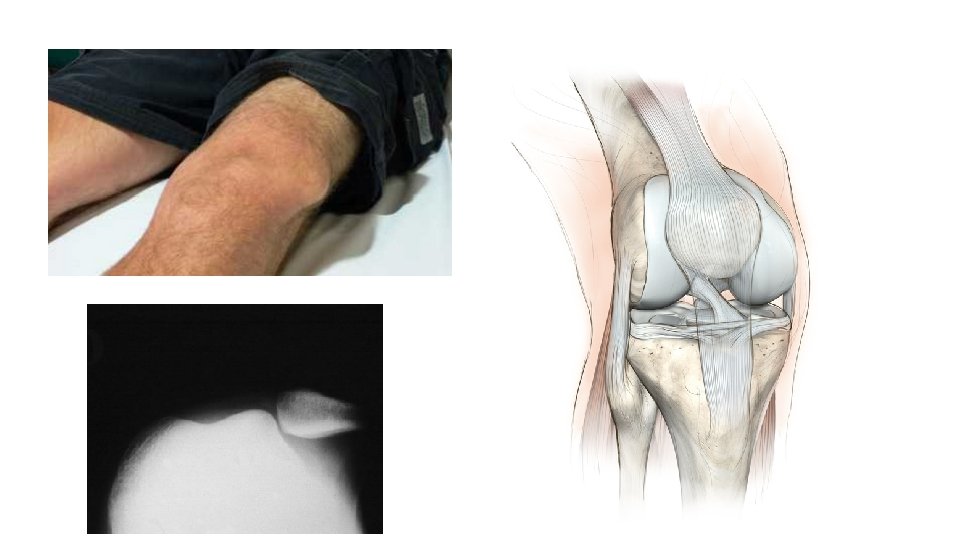

• Epaule • Coude • Patella • Hanche et PTH • Doigts •

• Epaule • Coude • Patella • Hanche et PTH • Doigts • Mâchoire • Tendon d’Achille